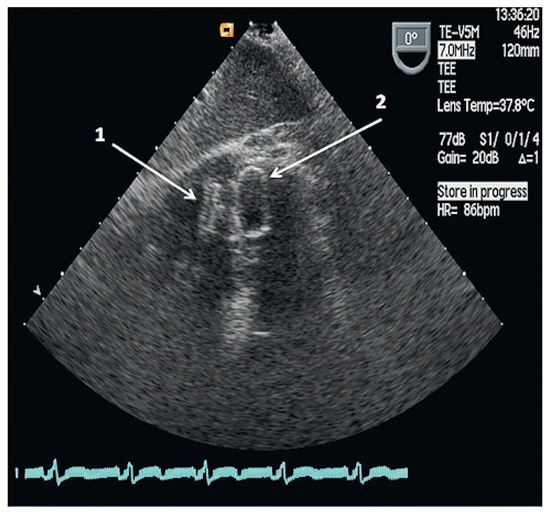

A Case for Incidental Coronary Angiography During Percutaneous Closure of the Patent Foramen Ovale?

by Nikesh Raj Shrestha, Thomas Pilgrim, Alexander Kadner and Bernhard Meier

A 42-year-old male had undergone a successful closure of a patent foramen ovale (PFO) seven years earlier for cryptogenic stroke. In spite of several risk factors an incidental coronary angiogram was not performed due to his young age (35 years at that time). [...] Read more.

A 42-year-old male had undergone a successful closure of a patent foramen ovale (PFO) seven years earlier for cryptogenic stroke. In spite of several risk factors an incidental coronary angiogram was not performed due to his young age (35 years at that time). Seven years later a myocardial infarction (MI) caused an apical ventricular septal defect (VSD) necessitating a surgical correction. Finally device closure became necessary due to patch dehiscence. Incidental coronary angiography on the occasion of PFO closure would have resulted i n timely coronary treatment by acetylsalicylic acid and a statin and perhaps coronary angioplasty. The MI and its complicated course could most likely have been prevented. Full article

Figure 1